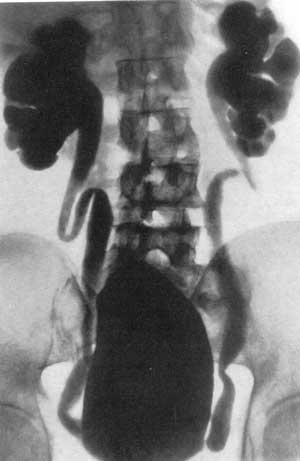

Экскреторная урография при нефроптозе: диагностические изображения